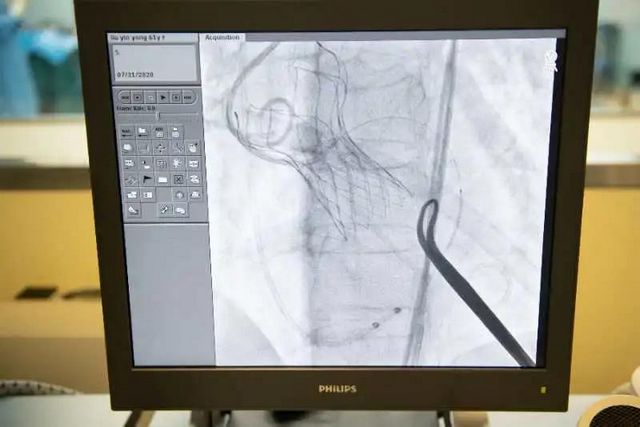

7月31日,刘阿姨在心脏大血管外科对症治疗了10多天后,通过医学影像科进行详细的术前评估,制定了详尽的手术方案,于风旭带领着由医院心脏大血管外科、心血管内科、麻醉科、超声医学科、介入医学科、手术室等组成的多学科团队在医院康健中心院区的复合手术室为刘阿姨进行了TAVI手术。

手术台上没了刀光血影,刘阿姨仅大腿上有一个4厘米左右的小切口,手术3个小时顺利完成。第二天刘阿姨的症状就明显缓解了,经过精心护理后,恢复正常的刘阿姨已出院回家。

瓣膜植入完成

该手术无需开胸、体外循环和心脏停跳,用于替换的人工心脏瓣膜从股动脉进入,通过导管一点一点送入到病变位置,输送距离远、输送环境复杂。要求手术者具备冠脉支架、球囊扩张等全面的心脏病诊治技术,需要一个强大的多学科协作团队来保驾护航。并且,医院的复合手术室将传统的外科手术室和介入治疗室有效地整合在了一起,集成外科、介入、放射影像等学科的优势于一体,为多学科同步联合开展复杂手术奠定了基础。医院强大的综合实力为TAVI手术成功开展的提供了强大的技术后盾。